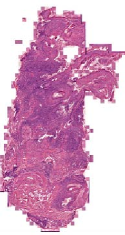

We demonstrate our WSI creation workflow on Leishmaniasis cases, as shown in Figures 1 and 4. An expert pathologist reviewed the cases and annotated granulomas as well as LD bodies on the stitched images and our generated images in Figure 4. To show generalizability of our approach, we also show results on core biopsies of breast, duodenum, stomach, liver, and lymph nodes (Figure 5).

| Breast | Duodenum | stomach | liver | lymph node | |||||

Curated dataset. Skin biopsies from 12 patients diagnosed with cutaneous leishmaniasis (spanning the disease differentiation spectrum) were acquired from Agha Khan University with Internal Review Board approval # 2024-9038-28175. Six of these biopsies, stained with hematoxylin & eosin (H&E), were scanned using Huron’s TissueScope digital scanner at 40X. A cheap-yet-clinical grade ($200) microscope (BS-2020MD Digital Microscope from BestScope International Limited, China) with a built-in digital 1.3 megapixel CMOS USB camera and 1W 5-LED illumination with Halogen Lamp 6V/20W was then used to capture videos for all 12 skin biopsies at 10X resolution. To show generalizability of our whole-slide image creation workflow for other common pathologies beyond cutaneous leishmaniasis, we also acquired videos for core biopsies of breast, liver, duodenum, stomach, and lymph node.